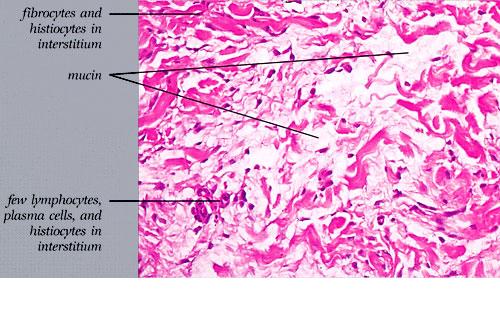

The mucin found in these six diseases represents an increase in the mucin that is normally present in the ground substance of the dermis. It consists of proteins bound to hyaluronic acid (hyaluronan), which is an acid mucopolysaccharide or glycosaminoglycan. As a result of the great water-binding capacity of hyaluronic acid, dermal mucin contains a considerable amount of water. This water is largely removed during the process of dehydration of the specimen; consequently, in routine sections, the mucin, because of its marked shrinkage, appears largely as threads and granules.

The mucin present in the six types of mucinosis stains a light blue in sections stained with H&E. It also stains with colloidal iron. It is Alcian blue-positive at pH 2.5 but negative at pH 0.5 and shows metachromasia with toluidine blue at pH 7.0 and 4.0 but no metachromasia below pH 2.0 . It is PAS negative (indicating the absence of neutral mucopolysaccharides) and aldehyde fuchsin negative (indicating the absence of sulfated acid mucopolysaccharides). The mucin is completely removed on incubation of histologic sections with testicular hyaluronidase for 1 hour at 37″C .